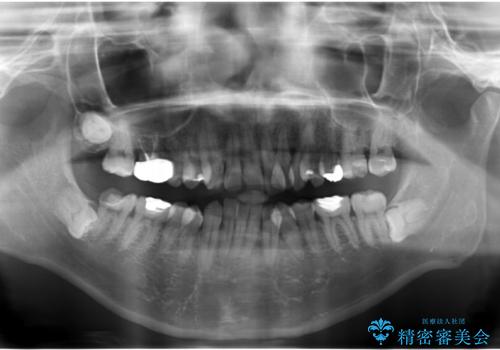

歯頚ラインが変えられないことや天然歯を削るリスクをご理解頂いた上で、オールセラミッククラウンによる補綴治療を行いました。(見えない奥歯のみ天然歯のままとしました)

下の前歯1本だけ歯軸を変えるために神経をとり根管治療を行っております。

治療前に埋伏している親知らずの抜歯をおすすめしましたが、ご希望されませんでした。

- ¥2,790,000 (仮歯×24本、根管治療×1本、土台×1本、クラウン×24本、セラミックインレー×1)費用は治療当時の料金となります